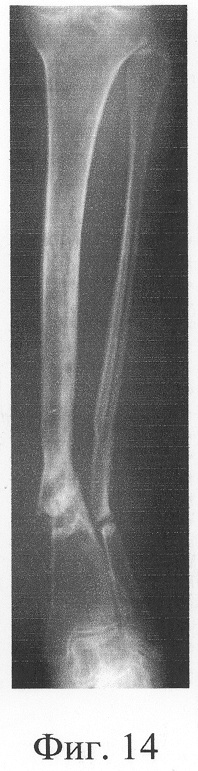

Больная П., 42 лет, поступила для оперативного лечения с диагнозом «атрофические ложные суставы обеих большеберцовых костей; сросшийся с укорочением 5 см перелом левой бедренной кости, хронический остеомиелит левой бедренной кости, фаза ремиссия; посттравматическая невропатия правого малоберцового нерва». В анамнезе – накостный, а затем дважды внеочаговый остеосинтез левой большеберцовой кости с исходом в ложный сустав; 4 операции внеочагового остеосинтеза правой большеберцовой кости, в том числе с костной пластикой; сроки фиксации в аппарате от 5 до 10 мес. Результат не достигнут: с обеих сторон сформировались ложные суставы (фиг.8-11 – клинические и фиг.12-15 – рентгенологические данные до лечения по предложенному методу).

Одномоментно выполнены операции: резекция ложных суставов обеих большеберцовых костей, резекция левой малоберцовой кости, комбинированный чрескостный остеосинтез костей обеих голеней, костная пластика ложных суставов деминерализованным костным аллотрансплантатом из трубчатой кости, предварительно в лабораторных условиях заселенным аутологичными мезенхимными стволовыми клетками, выделенными из костного мозга пациентки, с плотностью заселения 7-10 млн на 1 см3 трансплантата. В послеоперационном периоде потребовалась дополнительная коррекция положения фрагментов на правой голени, что привело к смещению трансплантата из костного паза. Дренажи удалены на 3-е сутки, швы сняты на 15 сутки, антибактериальная терапия под контролем клинического фармаколога с учетом анамнеза. Ходьба с дополнительными средствами опоры с 7 суток послеоперационного периода. Компенсация укорочения бедра обувью (фиг.16-17 – клинические и фиг.18-19 – рентгенологические данные в процессе лечения, трансплантаты отчетливо видны на рентгенограммах, отмечается нарастание плотности костной ткани в области трансплантатов).

Аппарат внешней фиксации с левой голени демонтирован через 3 месяца после операции при клинико-рентгенологической картине сращения перелома. Аппарат внешней фиксации с правой голени демонтирован через 7 месяцев после операции при клинико-рентгенологической картине сращения перелома (фиг.20-25 – результат лечения). При рентгенологическом и томографическом контроле в трансплантатах отмечалось постепенное нарастание плотности костной ткани с формированием костной мозоли на всем протяжении между трансплантатом и костными фрагментами (фиг.26-29 – динамика данных компьютерной томографии правой голени: отмечается нарастание плотности костной ткани в области трансплантатов и формирование регенерата между смещенным трансплантатом и костными фрагментами; фиг.30-33 – динамика данных компьютерной томографии левой голени: отмечается нарастание плотности костной ткани в области трансплантатов и формирование регенерата между трансплантатом и костными фрагментами).